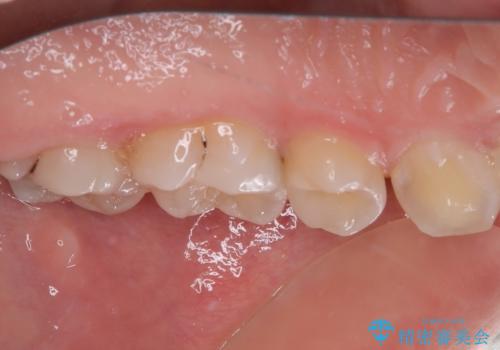

- 食事の度に物が挟まるとのことで来院された患者様です。

目視でも欠損が認められ、レントゲン写真からもむし歯が認められる状態でした。

患者様と相談の上、セラミックインレーで精密な修復治療を行うこととしました。

精密な型取りと、ラバーダム防湿下での接着操作により、歯と詰め物の隙間を最小限にとどめることができ、良好な長期予後が期待できます。